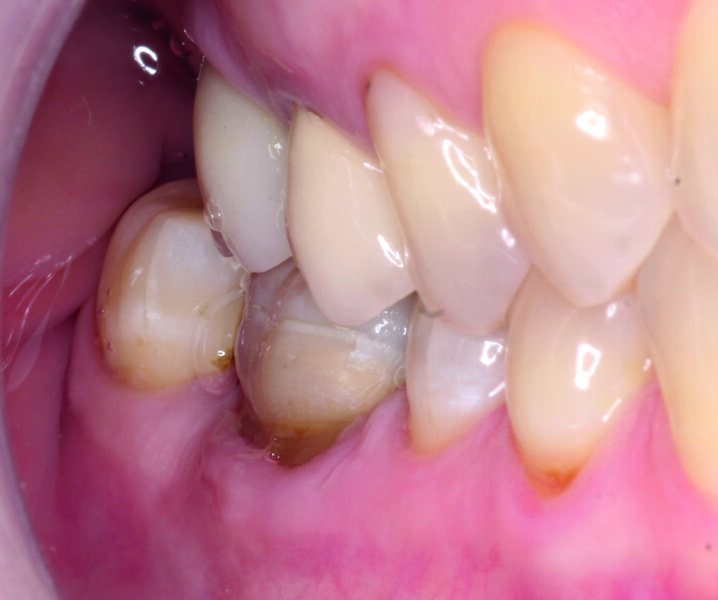

Fig. 1: Initial situation: failure of periodontal anatomical integrity due to overcontoured amalgam filling in tooth #45, and cracked and lost amalgam on tooth #46. (All images: Lucas J. Echandia & Martin I. Ibañez)

Records and diagnosis Radiographically, no carious lesions were detected. The periapical radiograph of tooth #46 showed a relatively non-homogeneous endodontic filling characterised by poor condensation and incomplete apical sealing because the gutta-percha did not fill the whole circumference of the apical foramina. Nevertheless, this tooth had been asymptomatic for 16 years, so it was decided not to opt for endodontic retreatment. The radiograph also showed an overcontoured filling in tooth #45.

The clinical examination revealed an amalgam filling over the asymptomatic root of tooth #46 and the overcontoured amalgam filling in tooth #45, which had facilitated inflammatory and hyperplastic changes to the surrounding gingival margin, and tooth #46 had lost several coronal areas of the residual hard tissue and most of its lingual wall and presented with some microcracks on the residual surface (Fig. 1). Tooth #45 did not show any clinical symptoms on the pulp vitality test.